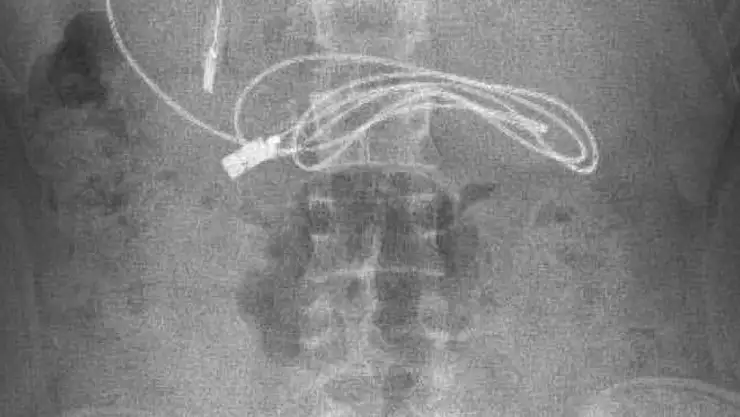

Çocuk, bölgede tek olan Fırat Üniversitesi Hastanesi Çocuk Gastroenteroloji Hepatoloji ve Beslenme Bölümüne sevk edildi. Burada da tetkik ve ön kontroller sonrası karnında yaklaşık 1 metre uzunluğunda düğümlü şarj kablosu ve lastik toka olduğu belirlenen 15 yaşındaki çocuğun tedavisine başlandı. Gastroenteroloji Hepatoloji ve Beslenme Bilim Dalı Başkanı Prof. Dr. Yaşar Doğan ve ekibi tarafından yapılan endoskopik operasyon sonucu Y.K.'nın karnında bulunan telefon şarj kablosu ve toka çıkarıldı. Kablonun düğümlü olduğunu ve ince bağırsağa dolandığı için zorlandıkları belirten Prof. Dr. Doğan, başarılı geçen operasyon sonrası hastayı taburcu ettiklerini ancak ilk kez böyle bir vaka ile karşılaştıklarını kaydetti.

Hasta hakkında bilgi veren Prof. Dr. Yaşar Doğan, "Hasta bize Diyarbakır'dan geldi. Orada yapılan incelemesinde karnında bir kablo yuttuğu ifade edildi. Oradaki hekim arkadaşlarımız bizi aradı. Biz de hastayı gerekli olan işlemleri yapmak üzere çağırdık. Hasta geldikten ve hazırlığı yapıldıktan sonra endoskopik işlemle gerekli olan müdahaleyi yaptık ve görüldüğü üzere kablo ile yanındaki saç tokasıyla birlikte çıkardık. İşlemden sonra hastada herhangi bir problem gelişmedi ve hastayı sağlıklı bir şekilde gönderdik" dedi.

Kablonun siyah renk almasının nedeni, mide asidi ile uzun süre temas olmasında dolayı bir renk değişikliğine uğramış. Bu tür vakalarla çok karşılaşıyoruz fakat böyle bir kablo yutan hasta ile ilk kez karşılaşıyoruz. Dolayısıyla bize ilginç gelen hastaydı. Açıkçası biz de işlem yaparken biraz zorlandık. Çünkü kablonun bir kısmı ince bağırsağa girmişti ve kabloda düğümlenme vardı. Bu düğümlenme olduğundan dolayı bağırsakla yapışıklık meydana getirmişti. Onu çıkarırken biraz zorlandık ama çıkarma esnasından herhangi bir komplikasyon gelişmedi" diye konuştu.